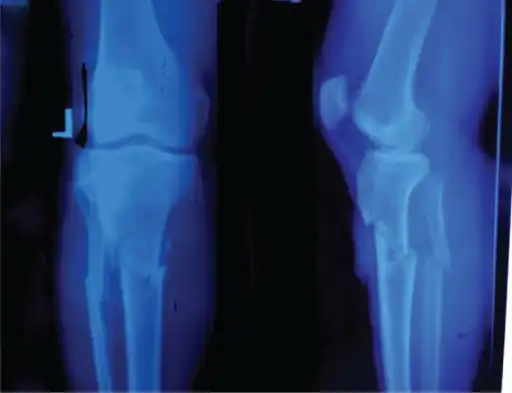

Knee showing tibial tuberosity avulsion fracture (and proximal tibial fracture)

X-ray of a 15-year-old male, showing an older avulsion fracture of the tibial tuberosity.